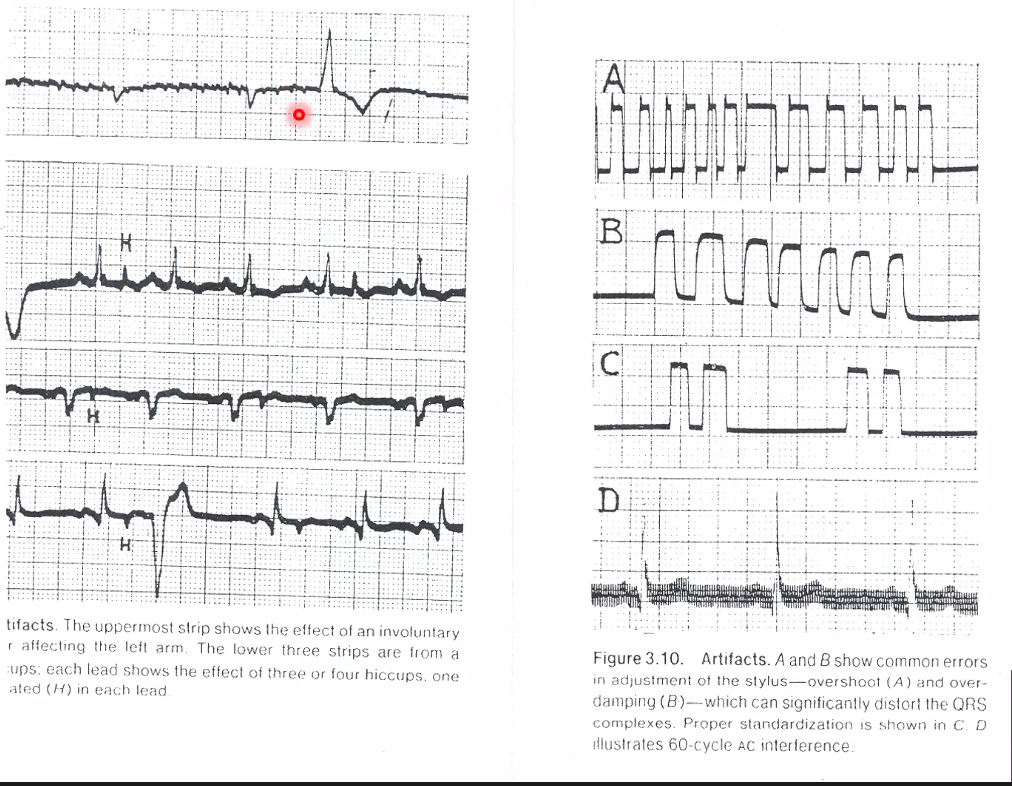

Q

ST segments

A

This is all artifact